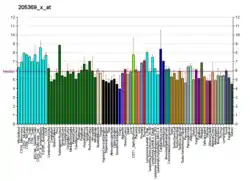

| DBT | |||||||||||||||||||||||||||||||||||||||||||||||||||

|---|---|---|---|---|---|---|---|---|---|---|---|---|---|---|---|---|---|---|---|---|---|---|---|---|---|---|---|---|---|---|---|---|---|---|---|---|---|---|---|---|---|---|---|---|---|---|---|---|---|---|---|

| |||||||||||||||||||||||||||||||||||||||||||||||||||

| |||||||||||||||||||||||||||||||||||||||||||||||||||